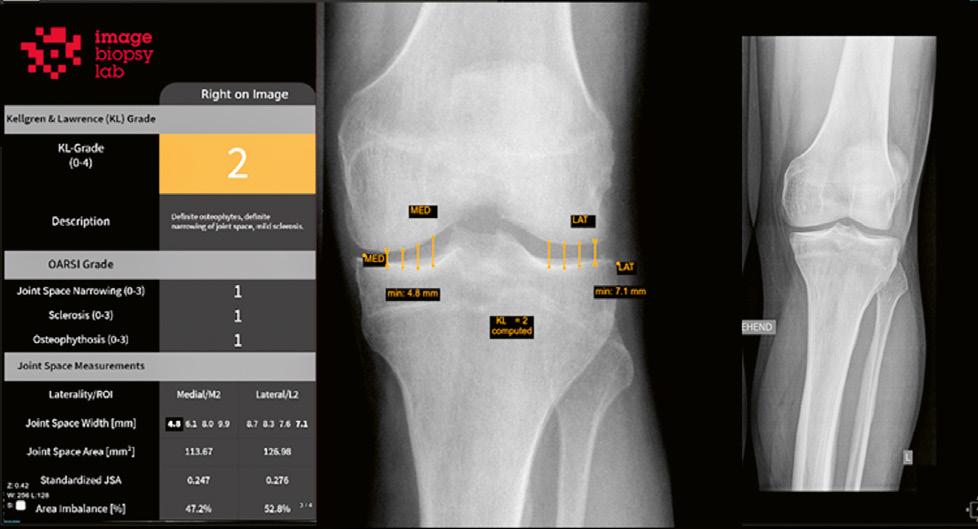

ImageBiopsy Lab · MSK Platform

Mit den neuen Medizinprodukten von ImageBiopsy Lab im Telepaxx Market Place erstellen Sie schnell und unkompliziert attraktive Auswertungen für Ihre Zuweiser:innen. Die KI-basierten Assistenzsysteme erkennen und vermessen MSK-Fragestellungen vollautomatisch, integrieren standardisierte Befundberichte nahtlos in Ihr RIS & PACS und liefern somit in wenigen Sekunden eine objektive Zusatzbefundung. An über 100 Standorten in Europa und den USA kommt die MSK Platform von ImageBiopsy Lab bereits zum Einsatz. Zur Nutzung schalten wir einfach Ihren vorhandenen Telepaxx Server frei. Alternativ dazu installieren wir die KI-Software bei Ihnen. Patientendaten verlassen in keiner Form Ihre Einrichtung.